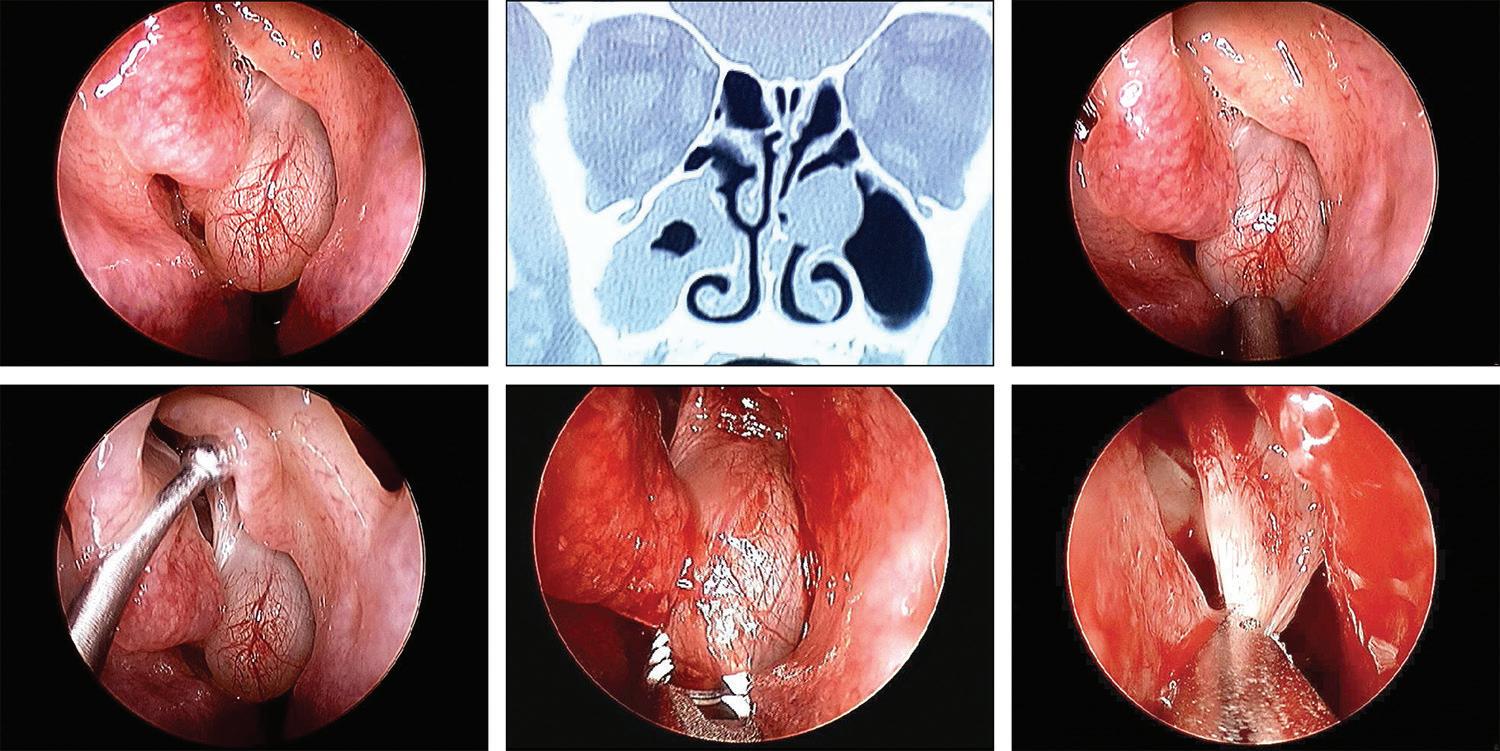

Endoscopic view of a mucocele obstructing a middle meatal antrostomy

A 38-year old woman presented with a 6-year history of chronic sinus problems. She had undergone bilateral endoscopic anterior ethmoidectomy and bilateral middle meatal maxillary antrostomies 4 years previously. Since she was having recurring sinus symptoms, her primary care physician referred her for evaluation.

Rhinoscopic evaluation revealed a large mucocele in the left middle meatus (figure, A). Computed tomography (CT) of the sinuses revealed a large soft-tissue mass obstructing the left middle meatal antrostomy and extensive mucosal thickening in the right maxillary sinus (figure, B).

The patient elected to undergo revision endoscopic sinus surgery. At the time of surgery, the mucocele obstructing the left middle meatus was identified (figure, C). A large left uncinate remnant was identified (figure, D) and was removed. The left mucocele was removed with a microdebrider (figure, E and F). The right max-

illary sinus was also debrided with the microdebrider. The patient had an uneventful postoperative course. Mucoceles are potentially obstructing and expansile lesions of the sinuses. These can occur naturally as mucus retention cysts or after sinus surgery, by ostial obstruction and formation of a lesion lined by low columnar epithelium.1 Mucoceles can be treated surgically by external or intranasal decompression.2

A B C D E F

Figure. A: Endoscopic view reveals the left middle meatal mucocele. B: CT scan shows the left middle meatal mucocele. C: The large obstructing mucocele is seen in this intraoperative view. D: The probe is retracting the large left uncinate remnant. E and F: The mucocele is removed with a microdebrider from inferiorly to its attachment superiorly.